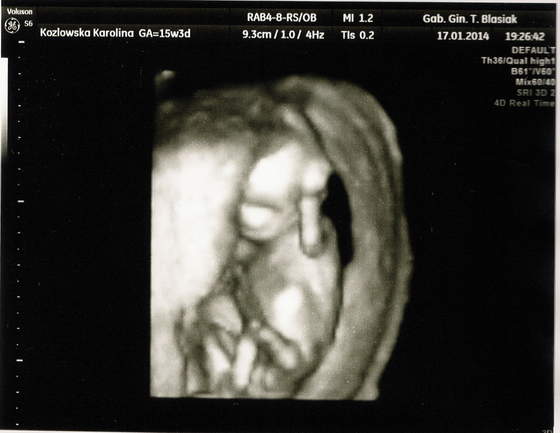

wizyty dzień do nocy, tamten na NFZ nic nie mierzył, tylko CRL a ten? Wszystkie kości pomierzył, paluszki policzył, główkę zmierzył, nawet mózg i móżdzek, serduszko dokładnie obejrzał ile komór, jak krew wpływa do serca, jak wypływa, posłuchaliśmy serduszka jak bije, czy budowa pępowiny jest ok, czy kręgosłup jest ok, jejku tyle rzeczy że aż nie mogłam się nadziwić, dostaliśmy chyba z 10 zdjęć z USG, i całą stronę A4 z opisami co badał, jakie są wyniki i czy jest ok. Najfajniejszy moment był jak przełączył na widok 3D i w tym samym czasie Maleństwo zakryło twarz raczkami tak jak małe dzieci się zakrywają i udają, że ich nie ma

niesamowite to było, aż wszyscy się zaczęliśmy śmiać :-)

oto kilka zdjęć naszej (chyba) córeczki